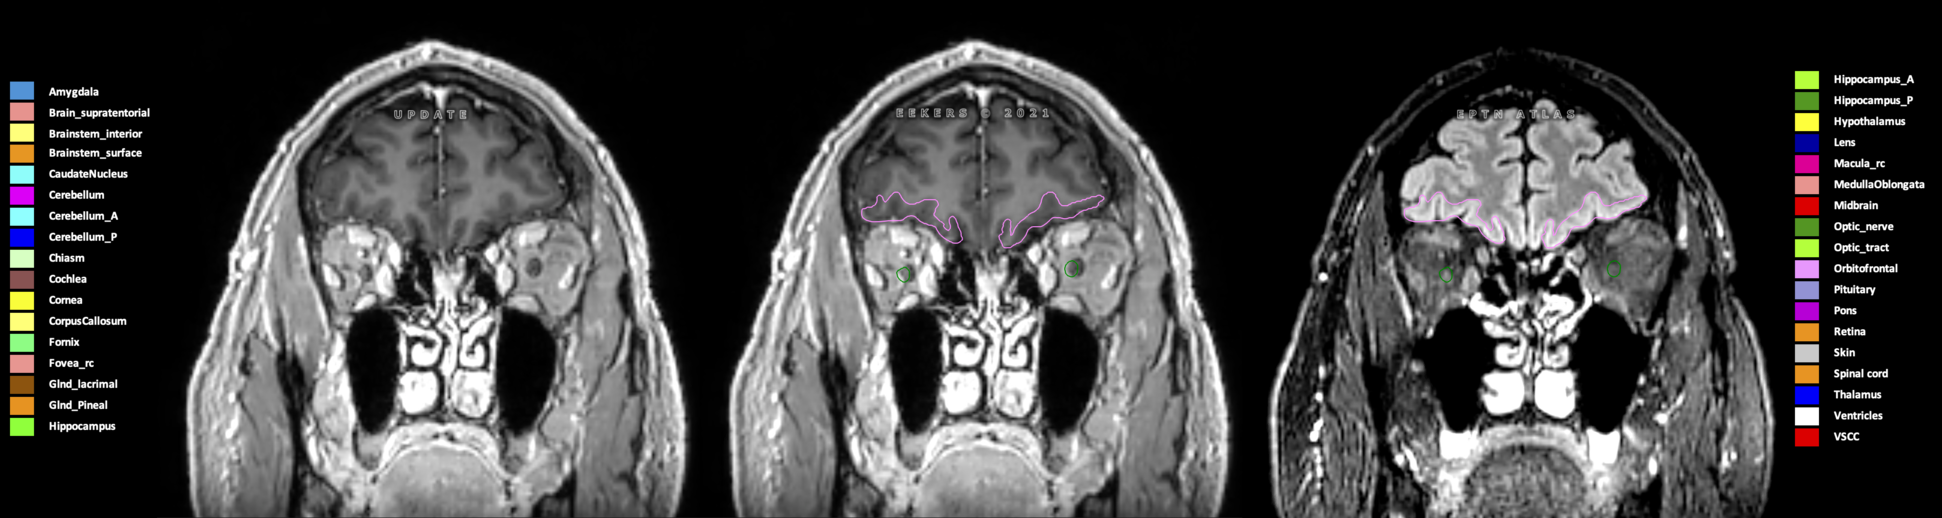

Eekers et al. have published an international neurological atlas for contouring of organs at risk in consensus with the European Particle Therapy Network (EPTN) in 2018 and an update in 2021. The purpose of this consensus atlas is to decrease inter- and intra-observer variability in delineating OARs relevant for neuro-oncology.

Included are all OARs known to be relevant for radiation-induced toxicity in neuro-oncology: brain, brainstem (midbrain, pons, medulla oblongata), chiasm, cerebellum (anterior & posterior), cochlea, cornea, hippocampus (anterior & posterior), hypothalamus, lens, lacrimal gland, optic nerve, pituitary, skin, and vestibular & semicircular canals. To further facilitate research on cognition, vision and radiological changes after irradiation of the brain, potential clinically-relevant OARs are included: amygdala, caudate nucleus, cerebellum (anterior & posterior), corpus callosum, fornix, macula, optic tract, orbitofrontal cortex, periventricular space (PVS), pineal gland, and thalamus.

Three-dimensional delineation of the 25 consensus OARs for neuro-oncology are shown on CT (WW/WL 120/40, 3000/600), 3T MR images, (T1Gd, T2FLAIR 1mm) and 7T MR (MP2RAGE 0.7 mm). All are presented in transversal, sagittal and coronal view.